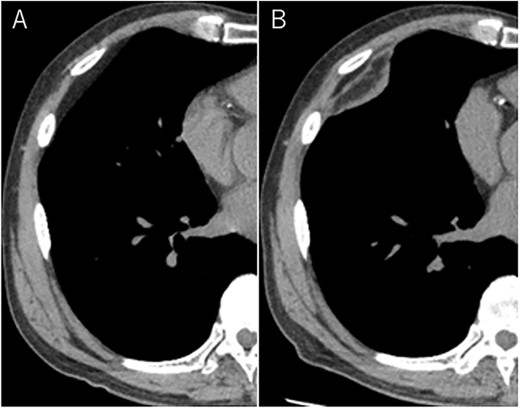

A 72-year-old man with a history of hypertension and left renal cancer (Stage I) was referred to us with a mass in the right chest wall on post-operative follow-up chest computed tomography (CT) for renal cancer. He had a smoking history of 20 pack-years and had no exposure to environmental fumes or dust. Physical examination results were unremarkable. The laboratory findings were within normal limits. Pulmonary function tests and cardiovascular examinations revealed normal results. Chest CT revealed mixed density mass (8.0 × 5.0 × 3.0 cm) located in front of thoracic wall in the third to sixth right intercostal space. The tumor can be revealed as thoracic wall fat (7.8 × 4.8 × 1.2 cm) on CT 1 year before (not considered as abnormal), and it was progressively increased in size and the density changed (Fig. 1A and B). Magnetic resonance imaging (MRI) showed a fatty mass of heterogenic density. T2 high foci (Fig. 2A) and irregular marginal enhancement of the tumor were observed (Fig. 2B). Maximal standard uptake value (SUVmax) of 18F-fluorodeoxyglucose positron emission tomography (FDG-PET) was 3.78 (Fig. 3). Based on these radiological image findings, we scheduled surgery with suspicion of liposarcoma. During the surgery, the patient was placed in the lateral decubitus position. We made 1.5-cm incision in the sixth intercostal space along the posterior axial line for thoracoscopy. We found dense adhesions between the chest wall tumor, lung (front part of all three lobes of the right lung) and diaphragm. We made a 30-cm incision in the fourth intercostal space and resected the tumor along with lung (wedge resection of the front part of all three lobes of the right lung), diaphragm and third to sixth ribs and intercostal muscle. The chest wall defect was 25 × 15 cm and the diaphragm defect was 8 × 5 cm. For reconstruction, the mesh was placed and sutured to the diaphragm and the chest wall. Pathological examination revealed the well-circumscribed tumor with fibrous adhesion between the ribs, lung and diaphragm (Fig. 4A). Microscopically, the tumor consisted of mature fat tissue. There were fat necrosis inflammatory changes in the marginal area of the tumor with foamy macrophages and multinucleated giant cells (Fig. 4B and C). Fluorescence in situ hybridization examination for murine double-minute 2 was negative. Based on these findings, a chest wall lipoma was diagnosed. The post-operative course was uneventful. The patient was followed up for 24 months without evidence of recurrence.

Chest MRI; (A) T2-weighted imaging showed several high signal foci in the tumor; (B) irregular marginal enhancement was observed.